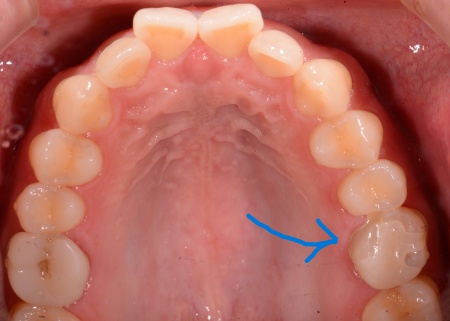

治療前

| 診断結果 | 拝見したところ、左上奥歯(第1大臼歯)が根の方まで割れている状態でした。 歯根が割れたまま放置すると、十分に噛むことができないだけでなく、周囲の歯茎が腫れて炎症が起きるおそれがあります。 以上のことから、割れてしまった歯を抜き、抜歯部位を補う治療が必要だと診断しました。 |

| 行った治療内容 | 患者様には、歯根が割れた歯の温存が難しく抜歯が必要であることをお伝えしたうえで、以下2つの治療方法を提案しました。 ①顎の骨に人工歯根「インプラント」を埋め込み、その上に被せ物を装着して欠損部を補う メリット:自分の歯のようにしっかりと噛むことができる デメリット:自費診療なので費用が高額になる。手術が必要なため、治療期間が長くなる ②抜歯部位前後の歯を土台として、橋渡しのような被せ物「ブリッジ」を装着する メリット:外科手術を行わないため、治療期間が短くなる デメリット:ブリッジの土台とするために健康な歯を削る必要がある それぞれのメリットとデメリットを丁寧に説明したところ、患者様は①のインプラントを選択されました。 まずはCT撮影を行い、歯や顎の骨の状態を詳しく調べます。 検査の結果、インプラントを埋め込むために必要な骨の量が十分にあることが確認できました。 次に左上奥歯1本を抜き、抜歯と同時にインプラントを埋め込む「抜歯即時埋入法」を用いて、インプラント手術を行います。 この方法であれば外科手術が1回ですむため、治療期間の短縮と噛み合わせの早期回復が可能です。 経過観察後、抜歯時の傷が回復してインプラントと骨がしっかりと結合したことを確認してから、インプラントに装着する被せ物を作製するために精密な型取りを行いました。 被せ物の素材には、耐久性に優れ天然歯のような見た目を再現できるセラミックを選択しています。 後日、完成した被せ物をインプラントに装着し、噛み合わせや使用感に問題がないことを確認して、治療を終了しました。 |